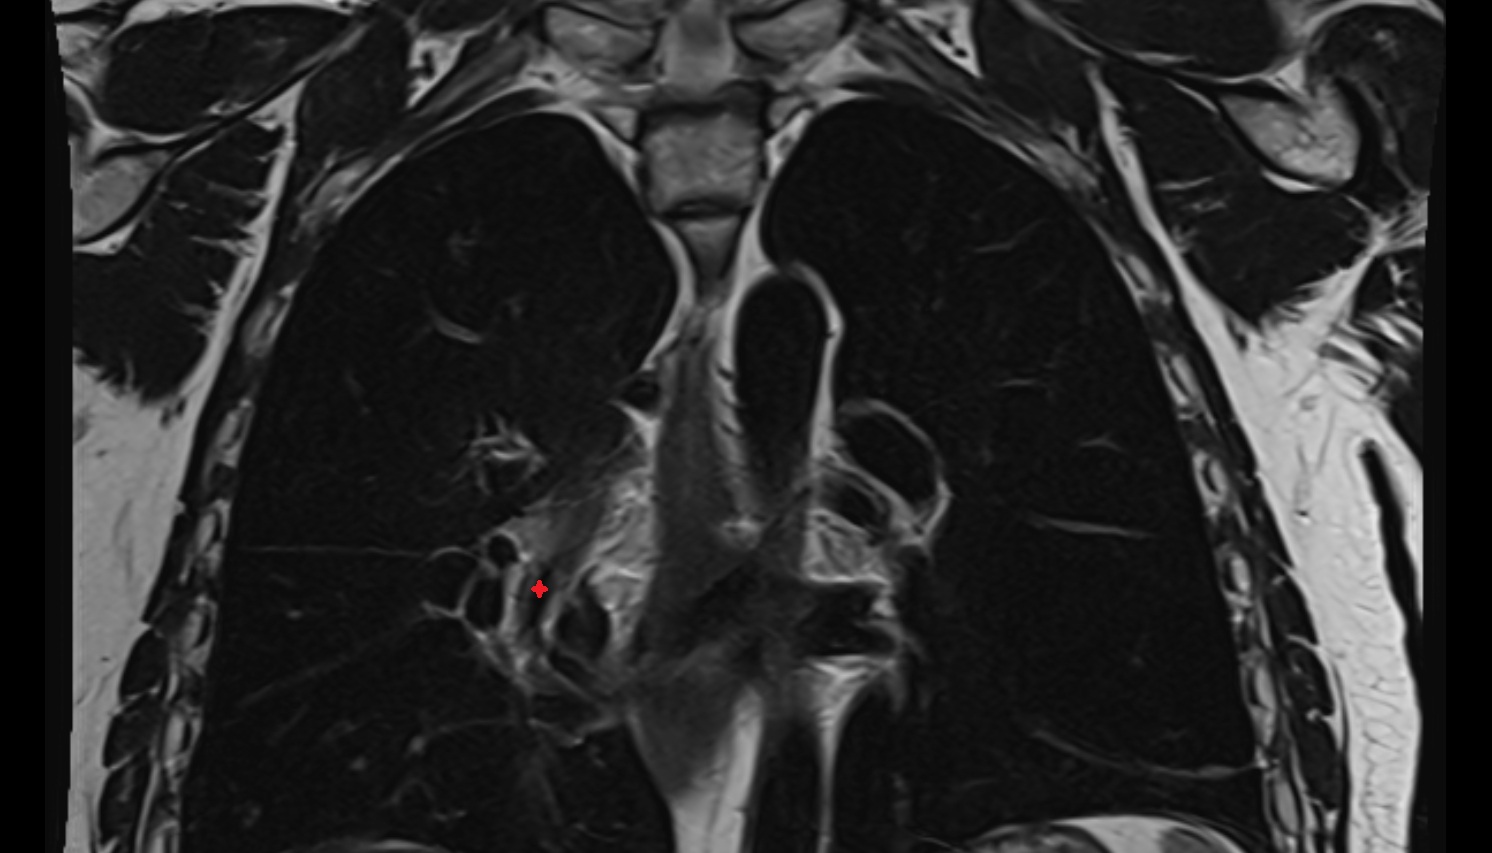

- Heart

- Left ventricle

- Right atrium

- Left atrium

- Right ventricle

- Pulmonary trunk

- Interventricular Septum

- Ascending aorta

- Arch of aorta

- Descending thoracic aorta